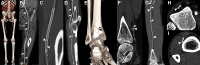

CT systems equipped with photon-counting detectors (PCDs), referred to as photon-counting CT (PCCT), are beginning to change imaging in several subspecialties, such as cardiac, vascular, thoracic, and musculoskeletal radiology. Evidence has been building in the literature underpinning the many advantages of PCCT for different clinical applications. These benefits derive from the distinct features of PCDs, which are made of semiconductor materials capable of converting photons directly into electric signal. PCCT advancements include, among the most important, improved spatial resolution, noise reduction, and spectral properties. PCCT spatial resolution on the order of 0.25 mm allows for the improved visualization of small structures (eg, small vessels, arterial walls, distal bronchi, and bone trabeculations) and their pathologies, as well as the identification of previously undetectable anomalies. In addition, blooming artifacts from calcifications, stents, and other dense structures are reduced. The benefits of the spectral capabilities of PCCT are broad and include reducing radiation and contrast material dose for patients. In addition, multiple types of information can be extracted from a single data set (ie, multiparametric imaging), including quantitative data often regarded as surrogates of functional information (eg, lung perfusion). PCCT also allows for a novel type of CT imaging, K-edge imaging. This technique, combined with new contrast materials specifically designed for this modality, opens the door to new applications for imaging in the future.